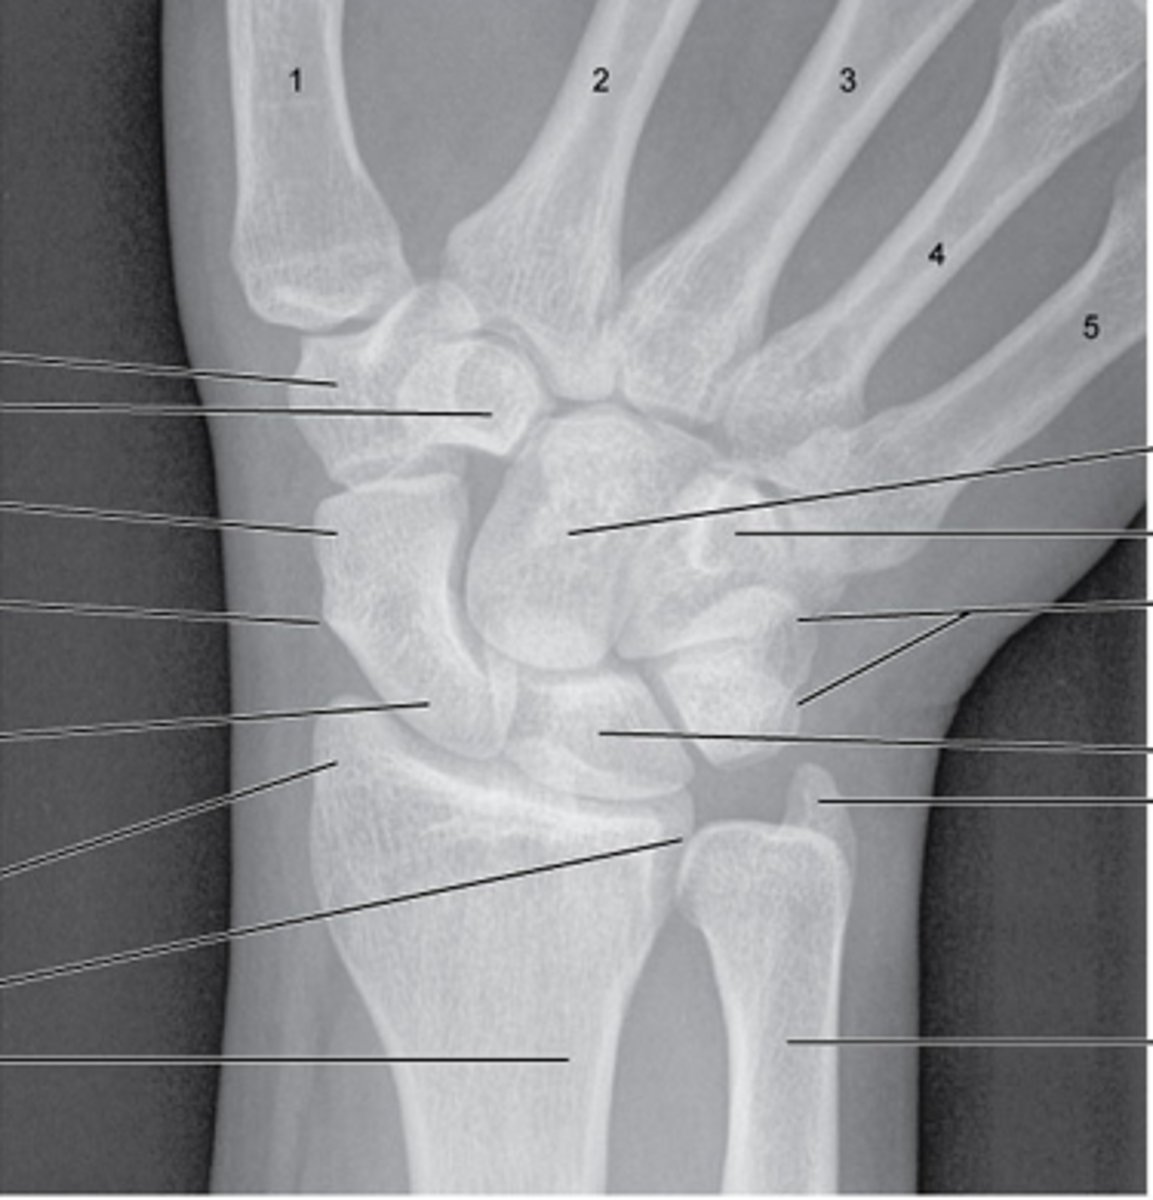

ankle/foot bones

review!